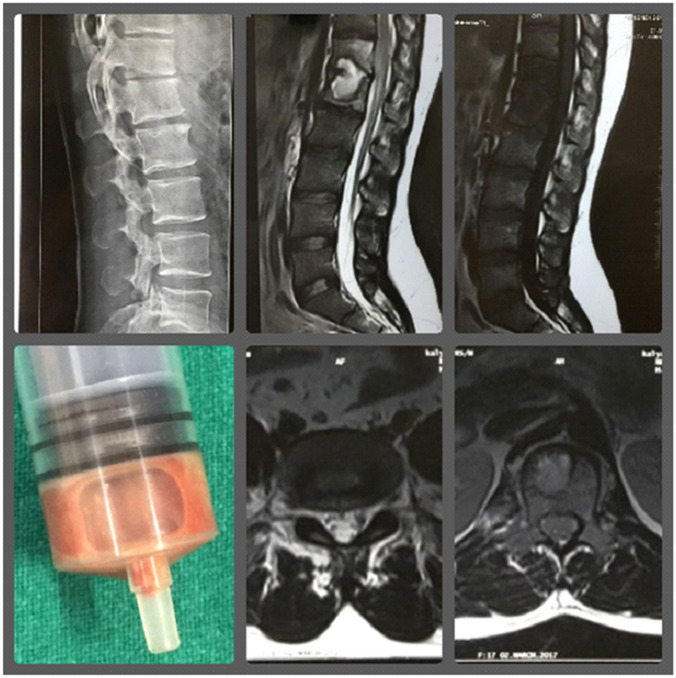

None of the patients included have been cited/included in any previous studies. All underwent aspiration of cold abscesses, core biopsy from extraspinal lesions or transpedicular CT guided biopsy from spinal lesions (Fig. 1). The spinal lesions were operated for debridement/decompression with/without instrumented stabilization, if indicated [13–17] (Fig. 2). Pus, fluid, cartilage, synovium, intervertebral disc material, granulation tissue, caseous tissue and bony tissue from the affected bone were sent for histopathology (at UCMS), and AFB smear, mycobacterial culture, CBNAAT and LPA at National Institute of Tuberculosis and Respiratory Diseases (NITRD), New Delhi [18,19]. All samples collected underwent all the above-mentioned tests. Standard operating procedures were also followed during specimen collection, transport and processing [18,19].

Fig. 1.

A 36-year-old male, a presumptive case (group A) of Pott’s spine D12-L1 with grade 1 paraplegia. Pt presented on 12/3/17 with low backache for 9 months. O/E-tenderness at D12, L1. Pt was elsewhere prescribed on Cat1 ATT since 7/3/17. CT-guided biopsy was done from D12 vertebrae on 16/3/17. CBNAAT and LPA TB positive, sensitive to R and H. Smear AFB positive, liquid culture negative, histology consistent for TB. PT was continued on Cat1 ATT